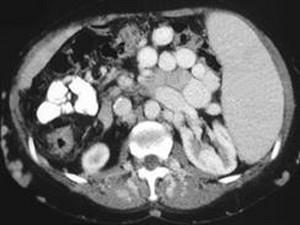

问题 男,50岁,患乙肝多年,现腹胀,右上腹痛,消化不良,消瘦、乏力、贫血、黄疸,血清转氨酶升高,白蛋白/球蛋白比值倒置。CT检查如下图,最可能的诊断是 ( )

选项 A、肝硬化、门脉曲张、脾大 B、肝硬化、脾大 C、肝硬化、腹膜后淋巴结肿大 D、肝硬化、肝癌、腹膜后淋巴结肿大 E、肝硬化、肝癌

答案 A